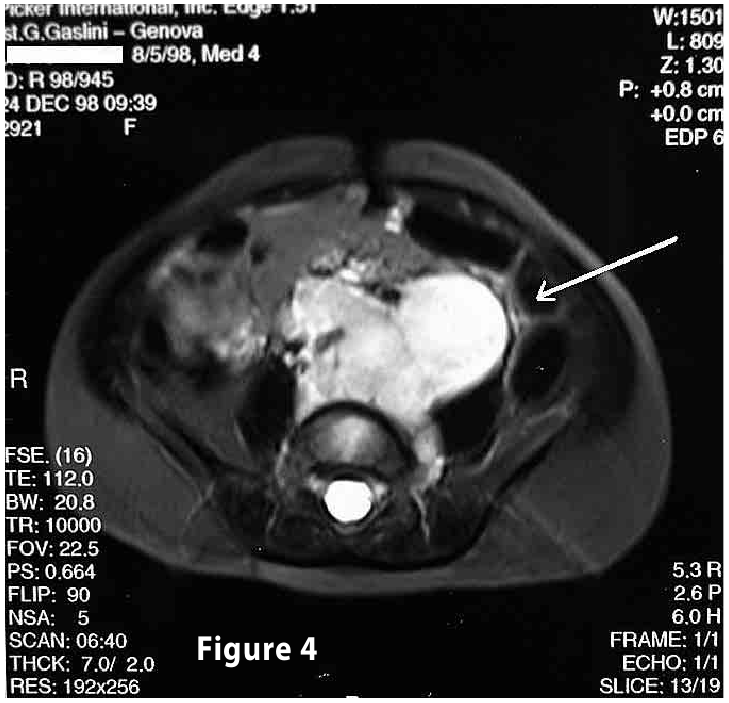

Complete objective response of neuroblastoma to biological treatment.

Figure4